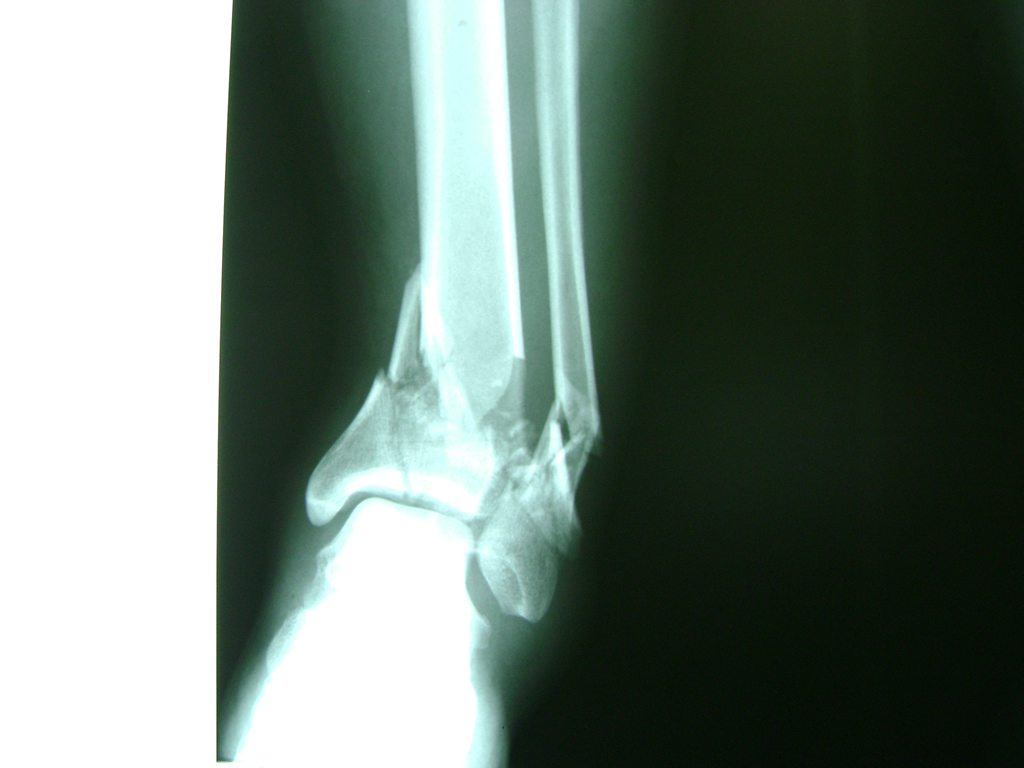

Una fractura de tobillo es la rotura de uno o más de los huesos del tobillo. Estas fracturas pueden ser:

- Los extremos de los huesos están desalineados entre sí (desplazados).

- La fractura se extiende hasta la articulación del tobillo (fractura intra-articular).

Cuando se necesita cirugía, es probable que esta implique el uso de clavijas de metal, tornillos o placas para sostener los huesos en su lugar mientras la fractura se consolida. Los elementos de soporte pueden ser temporales o permanentes.